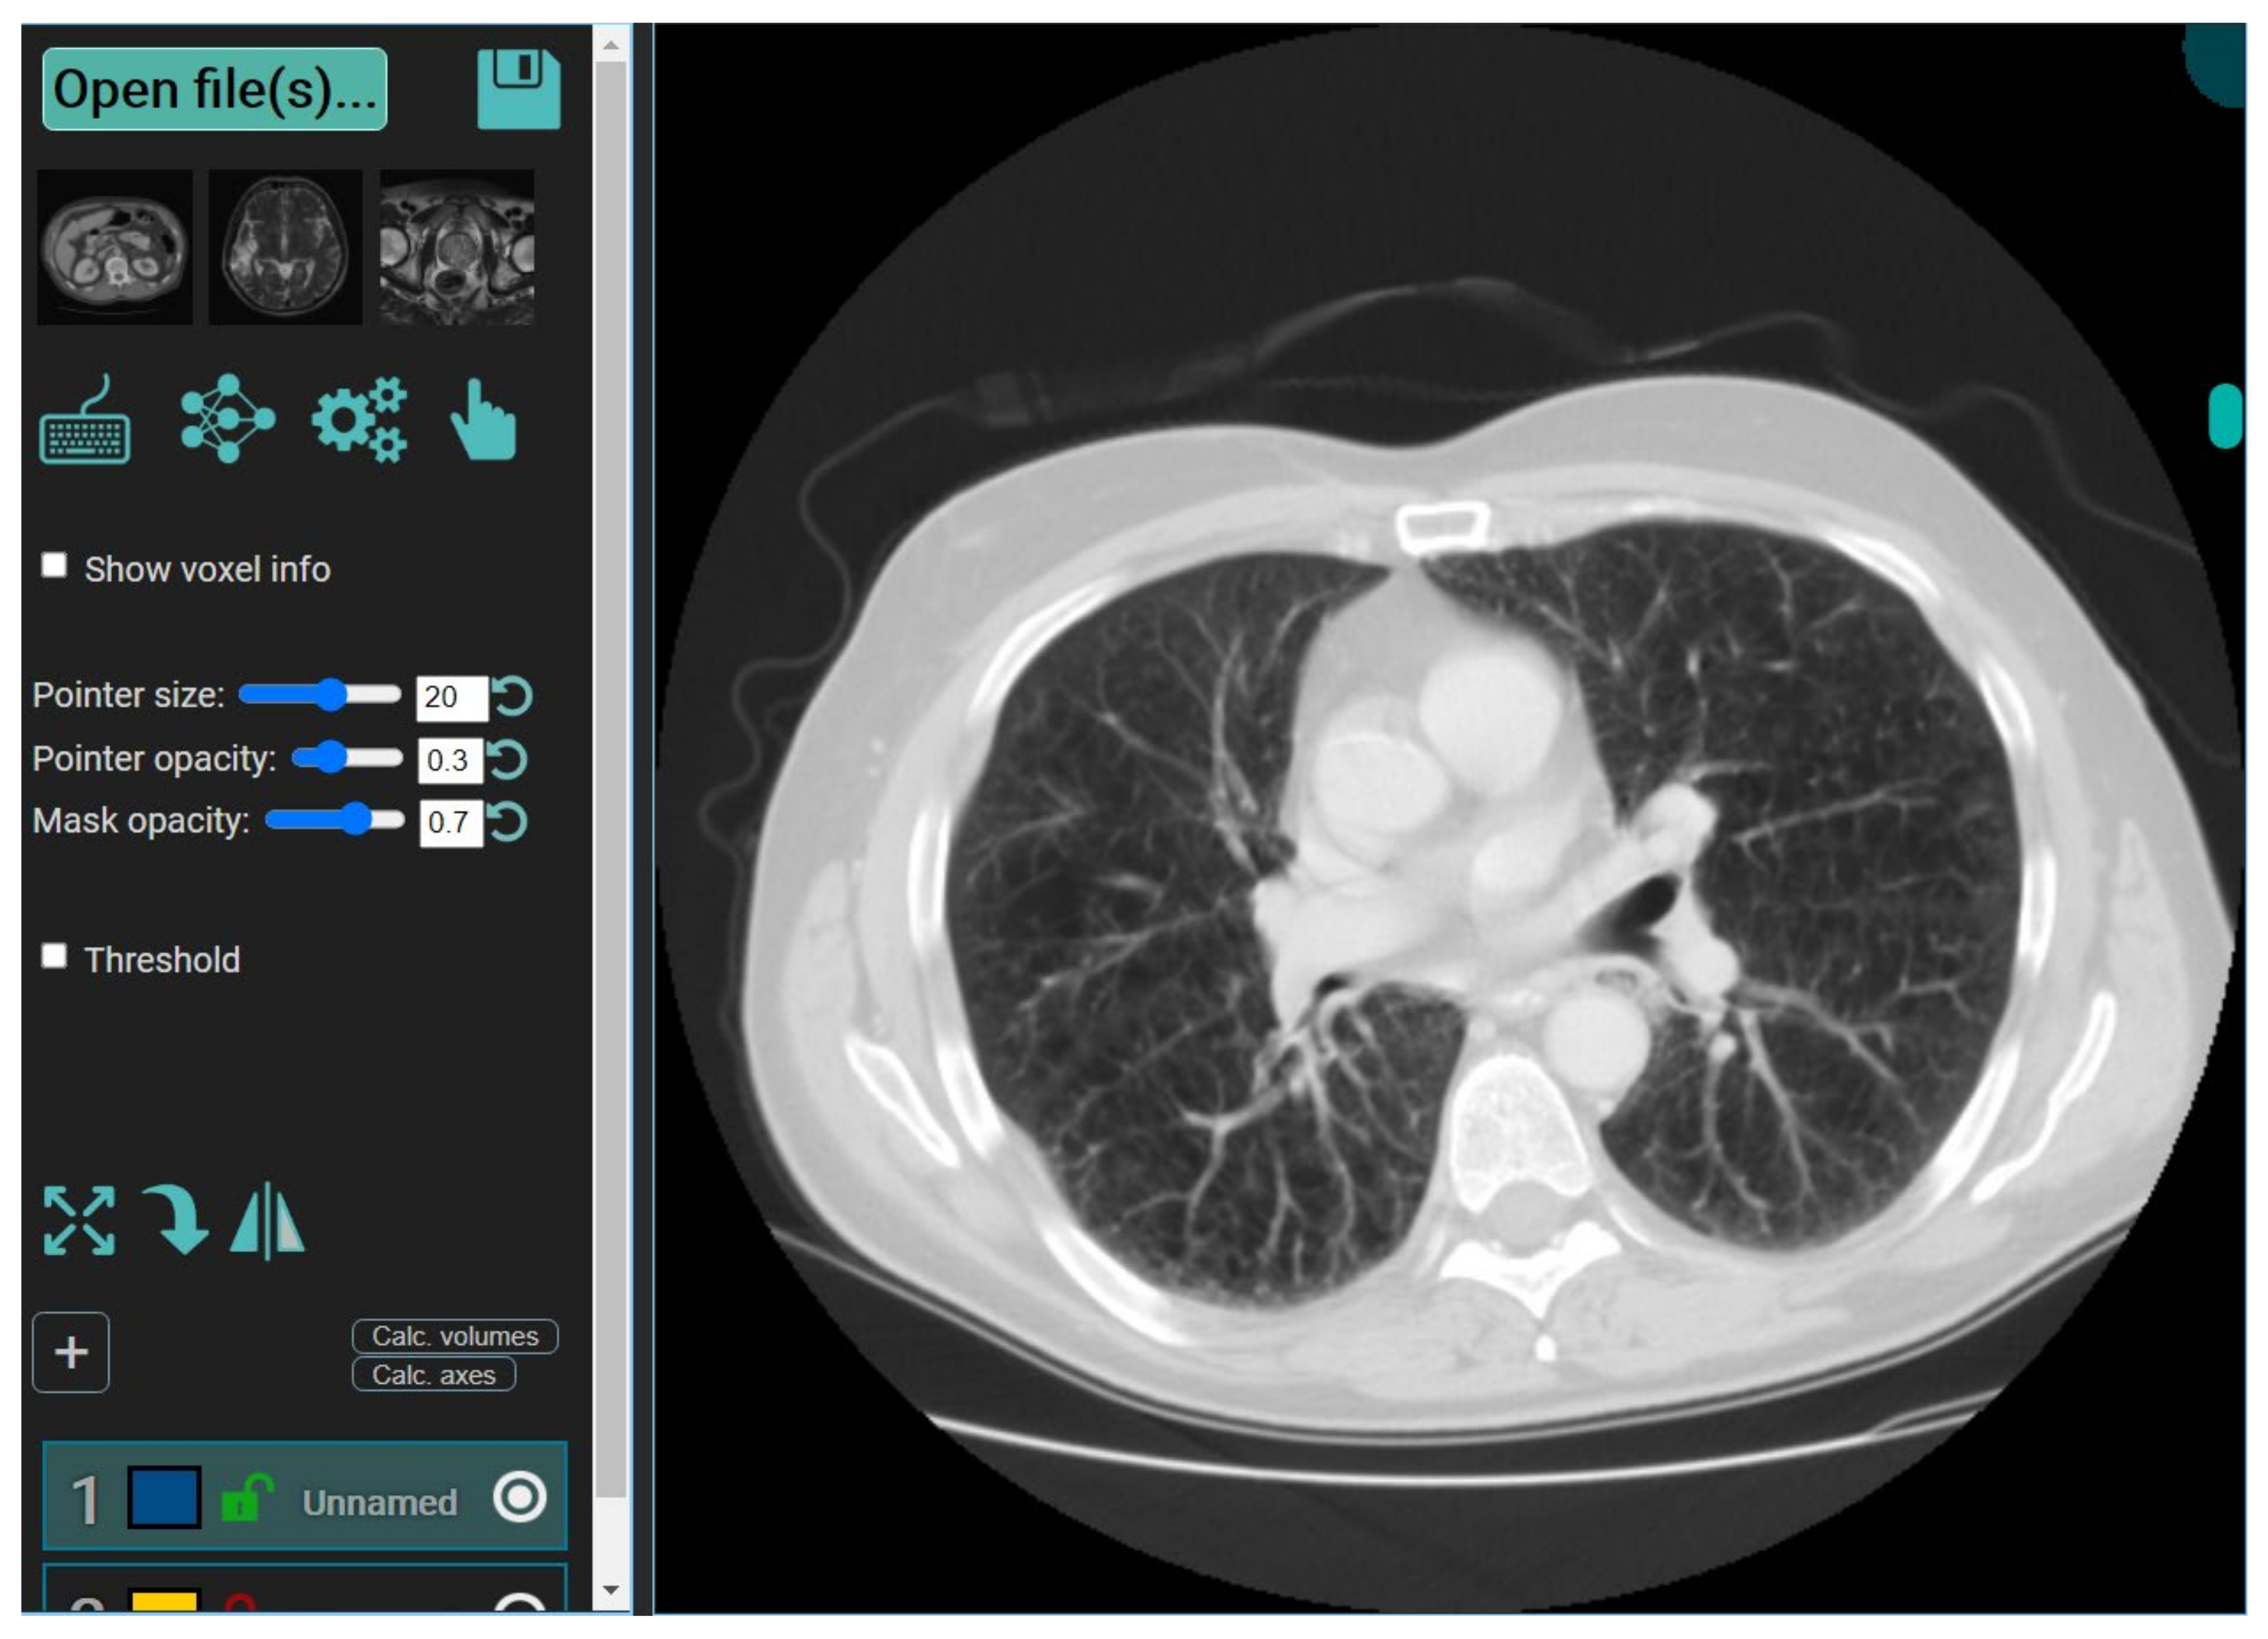

3.2.7. MedSeg—A Web-Based AI Segmentation Tool

4. Results and Performance Evaluation